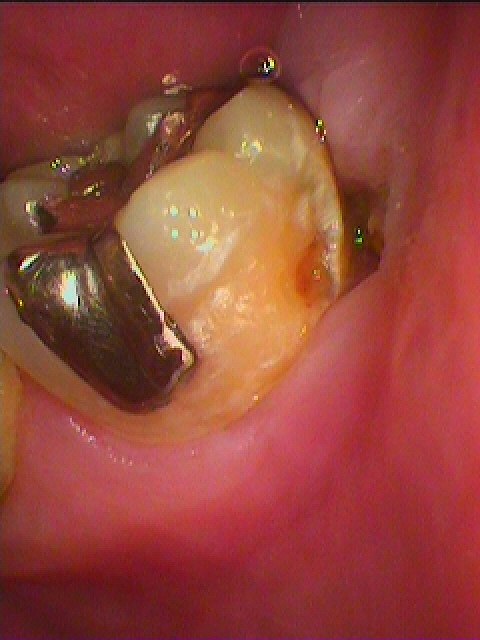

ブログ一覧|広島市安佐南区の歯科医院 ブログ一覧 トップ ブログ一覧 お知らせ スタッフブログ ブログ一覧 お知らせ 2020/01/27 右上1,2番 ジルコニアクラウン連冠の作成 ジルコニアのブロックからの削り出しより始めます お知らせ 2020/01/25 左下6欠損の5,7番ジルコニアブリッジの作成 強度的にも審美的にも問題ないきれいなジルコニアブリッジを作成していきます お知らせ 2020/01/25 右下6,7番インプラント部の上部構造をオールセラミッククラウンにて仕上げていきました お知らせ 2020/01/24 左下親知らずの水平埋伏難抜歯 このような親知らずは大学病院レベルになりますが、抜歯していきます お知らせ 2020/01/24 右下親知らずの水平埋伏難抜歯 日本人は親知らずが真横に傾くことが多いです お知らせ 2020/01/23 1月22日 水曜日 安芸高田市の介護医療院八千代にて、ラベンダー歯科から高齢者の口腔ケアの実践として講演会を開く機会を与えていただきました うちの衛生士が発表から、その実践を行いました いつも職員さんをはじめ八千代会さんには感謝しかないです お知らせ 2020/01/23 1月22日 水曜日 安芸高田市の介護医療院八千代にて、ラベンダー歯科から高齢者の口腔ケアの実践として講演会を開く機会を与えていただきました うちの衛生士が発表から、その実践を行いました お知らせ 2020/01/22 昔入れた銀歯の下は大きく虫歯になっていることがあります 右上6番セラミック治療 << 1 2 3 4 5 … 357 358 359 360 361 … 870 871 872 873 874 >> Web診療予約 初めての方へ 選ばれ続ける理由 院内設備について 歯が痛いしみる一般歯科 歯がぐらぐらする歯周病 健康な歯を保ちたい予防歯科 子供の虫歯予防をしたい小児歯科 銀歯をセラミックに審美歯科 白い歯を目指しませんか?ホワイトニング 矯正専門医がいるので安心矯正歯科 抜けた歯を補いたいインプラント・入れ歯 医院案内 スタッフ紹介 メリィハウス歯科クリニックオフィシャルホームページ ラベンダー歯科クリニックオフィシャルホームページ お知らせ・ブログ ホーム 診療科目 一般歯科 歯周病治療 予防治療 小児歯科 審美治療 ホワイトニング 矯正歯科 入れ歯・インプラント マウスピース矯正 初めての方へ 院長・スタッフ 設備紹介 医院案内・アクセス メニューを閉じる